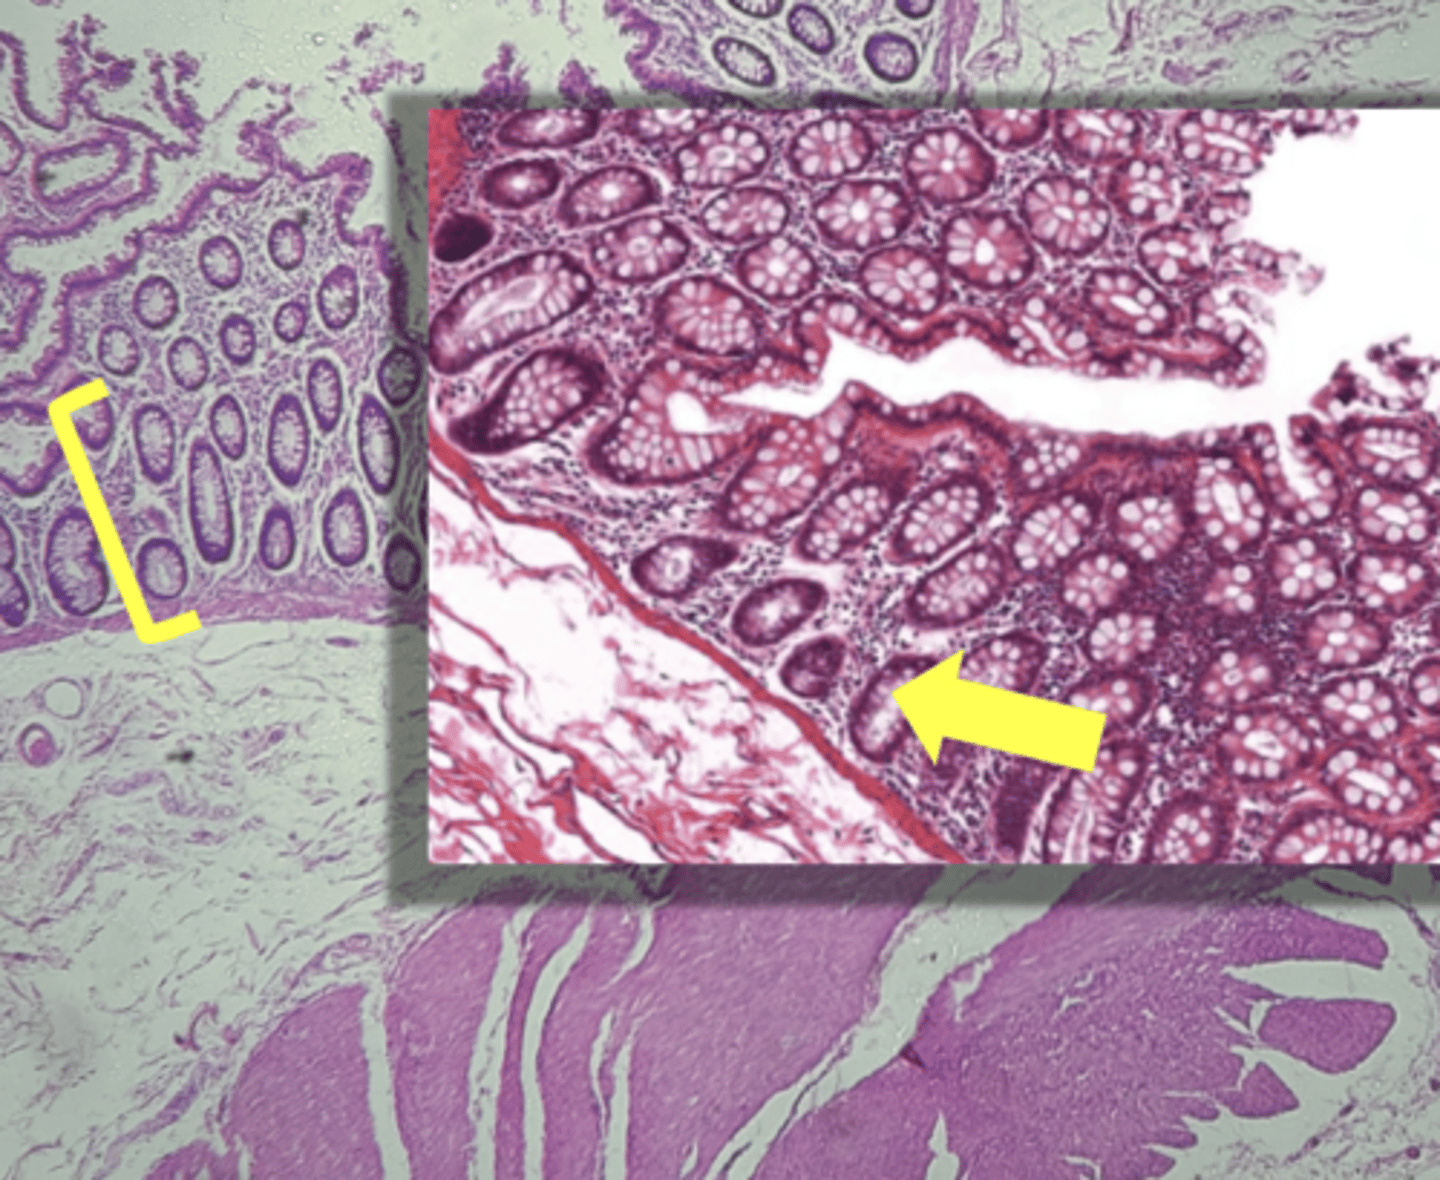

colon- large intestine

name the tissue

circular layer

(Lg. intestine)

longitudinal layer

mucosa

(lg intestine)

Submucosa

muscularis externa

goblet cells-mucus (LARGE # KEY CHARACTERISTIC)

name the cell & what it secretes

intestinal crypts

muscularis mucosae